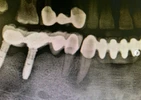

Fotoğraflar